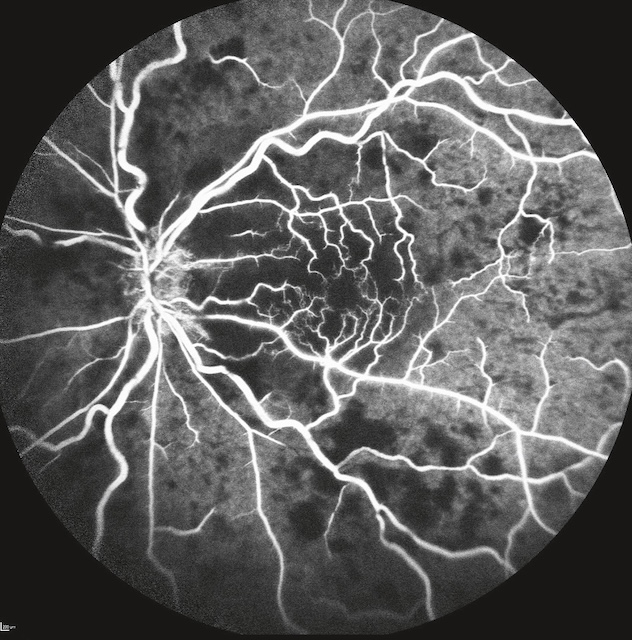

b Occlusion de la veine centrale de la rétine (OVCR) ou d’une de ses branches (fig. 8.7 à fig. 8.10 et e-fig. 8.11)

Image issue d’une angiographie à la fluorescéine montrant le fond d’œil d’un patient atteint d’une occlusion veineuse centrale de la rétine (OVCR) de type ischémique. Les vaisseaux veineux sont nettement dilatés, tortueux, et imprégnés de fluorescéine, contrastant fortement avec de larges zones de non-perfusion capillaire visibles en arrière-plan, traduisant une ischémie diffuse. Le centre de la rétine apparaît particulièrement appauvri en vascularisation, avec des territoires capillaires irréguliers et interrompus. Cette cartographie vasculaire altérée est typique des formes graves d’OVCR, avec un risque élevé de néovascularisation secondaire si non prise en charge rapidement.